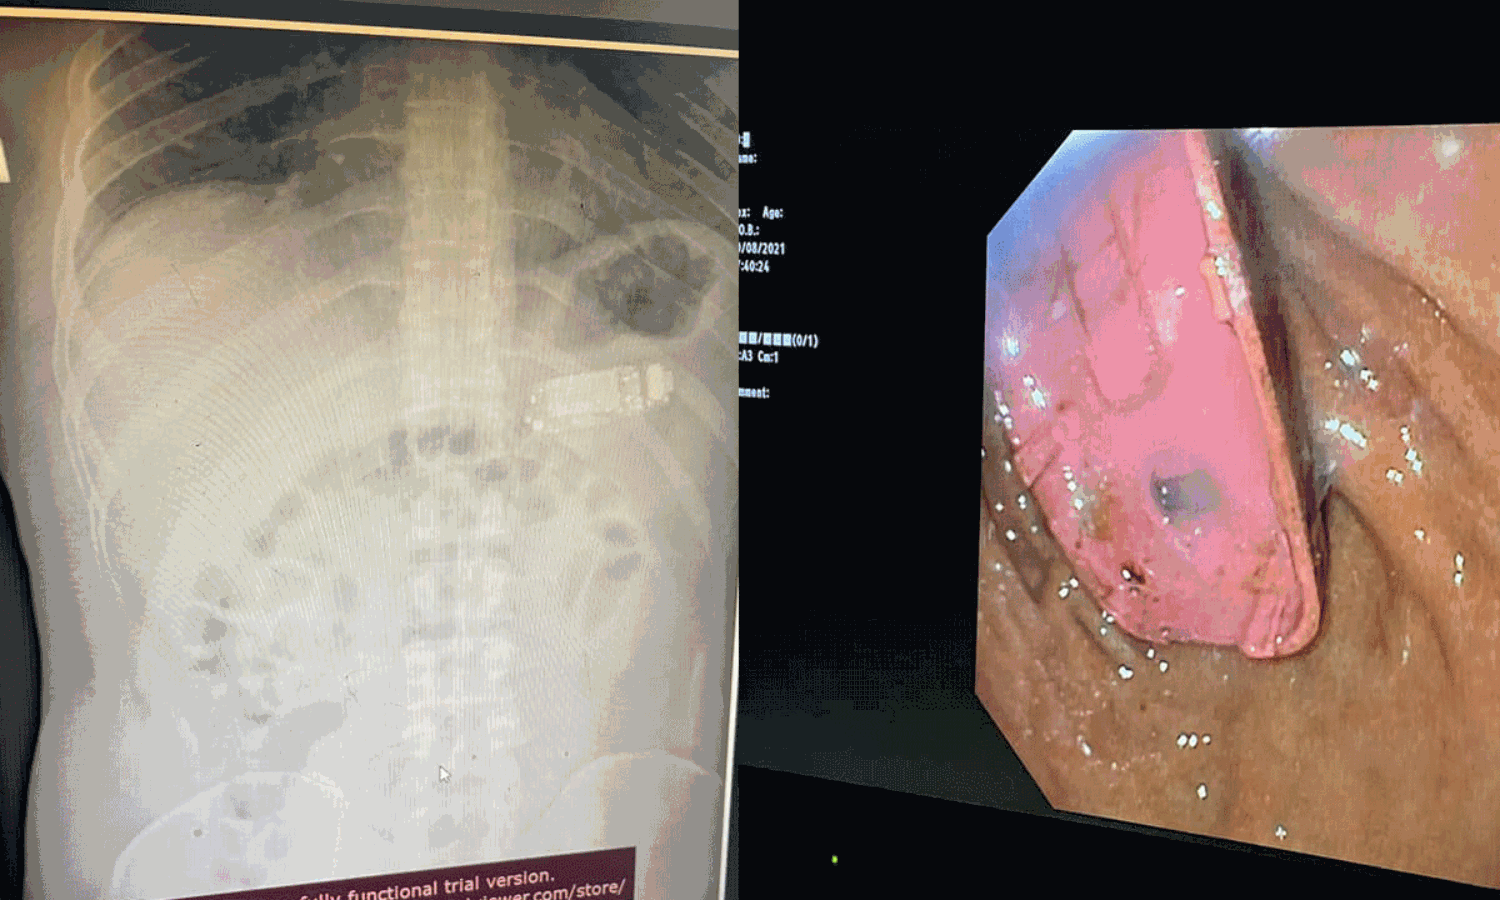

കൊസോവേ: പ്രിസ്ടീന നിവാസിയായ 33 വയസ്സുകാരൻ ഫോൺ വിഴുങ്ങി, രണ്ടു മണിക്കൂർ നീണ്ട ശസ്ത്രക്രിയയിലൂടെ പുറത്തെടുത്തു. ശസ്ത്രക്രിയ നടത്തിയ ഡോക്ടർ സ്‌കെൻഡർ ടെലാക്കു ഫോട്ടോയടക്കം ഫേസ്ബുക്കിൽ പോസ്റ്റിട്ടതോടെയാണ് വിവരം ലോകമറിഞ്ഞത്.

വയറുവേദന വന്നതിനെ തുടർന്ന് ഇയാൾ സ്വയം പ്രിസ്ടീനയിലെ ആശുപത്രിയിലെത്തുകയായിരുന്നു.

വയറ്റിൽ എന്തോ വസ്തുവിന്റെ സാന്നിധ്യമറിഞ്ഞ് നടത്തിയ സ്‌കാനിങ്ങിലാണ് ഫോൺ കണ്ടെത്തിയത്. തുടർന്ന് ഡോക്ടർമാർ ഫോൺ ബാറ്ററിയിലെ കെമിക്കലുകൾ മനുഷ്യശരീരത്തിന് ഏറെ അപകടകരമായതാണെന്ന് യുവാവിന് മുന്നറിയിപ്പ് നൽകിയിരുന്നു.

എന്നാൽ ശസ്ത്രക്രിയയിലൂടെ മൊബൈൽ പുറത്തെടുക്കുകയായിരുന്നു. ഡോക്ടർ ഫേസ്ബുക്കിൽ പങ്കുവെച്ച ചിത്രങ്ങളിലും എക്‌സറേയിലും എൻഡോസ്‌കോപ്പിയിലും വയറ്റിൽ ഫോണുള്ളത് വ്യക്തമാണ്.

ഫോൺ നീക്കം ചെയ്യുന്ന ശസ്ത്രക്രിയ ചിത്രീകരിച്ചിട്ടുണ്ട്. ഏത് ഫോണാണെന്ന് വ്യക്തമല്ലെങ്കിലും നോക്കിയ 3310 ആണ് വിഴുങ്ങിയതെന്ന് കരുതുന്നു.